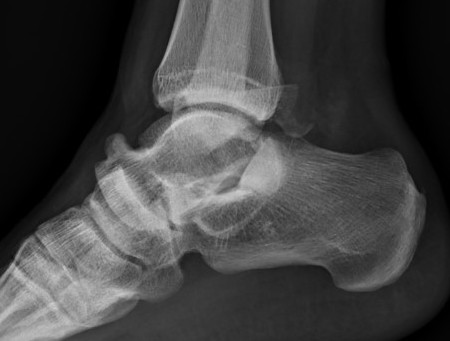

Fibular fracture and subtalar loose bodies after lateral subtalar dislocation

Congruent reduction

CT post reduction

Ensure

- congruent reduction

- look for fractures of talus / calcaneum

- look for intra-articular fragments